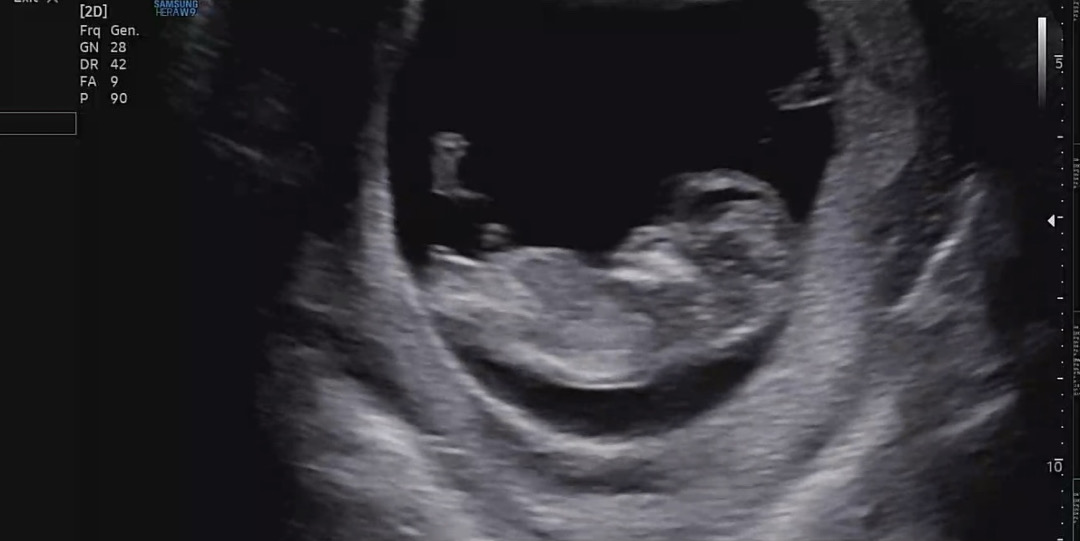

11주 각도법 봐주실래요🙏🥹

반전이 많은 주수인 거 알고 재미로 보려고 합니당.. 어느쪽이든 상관 없으나 ㅠㅠ 마미들은 어때보이시나요 ..? 🥹😳

딸인거같아요!